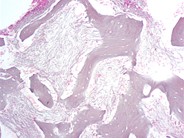

Marrow Changes in Renal Osteodystrophy - 5.

Category: Red Cell: Other Disorders > Bone/metabolic disease > Anemia of renal osteodystrophy

In this high power view two osteoclasts are noted in the left center of the image. Note the scalloping of the trabeculae and the presence of osteoblasts lining the trabecular borders. (H&E 40x)